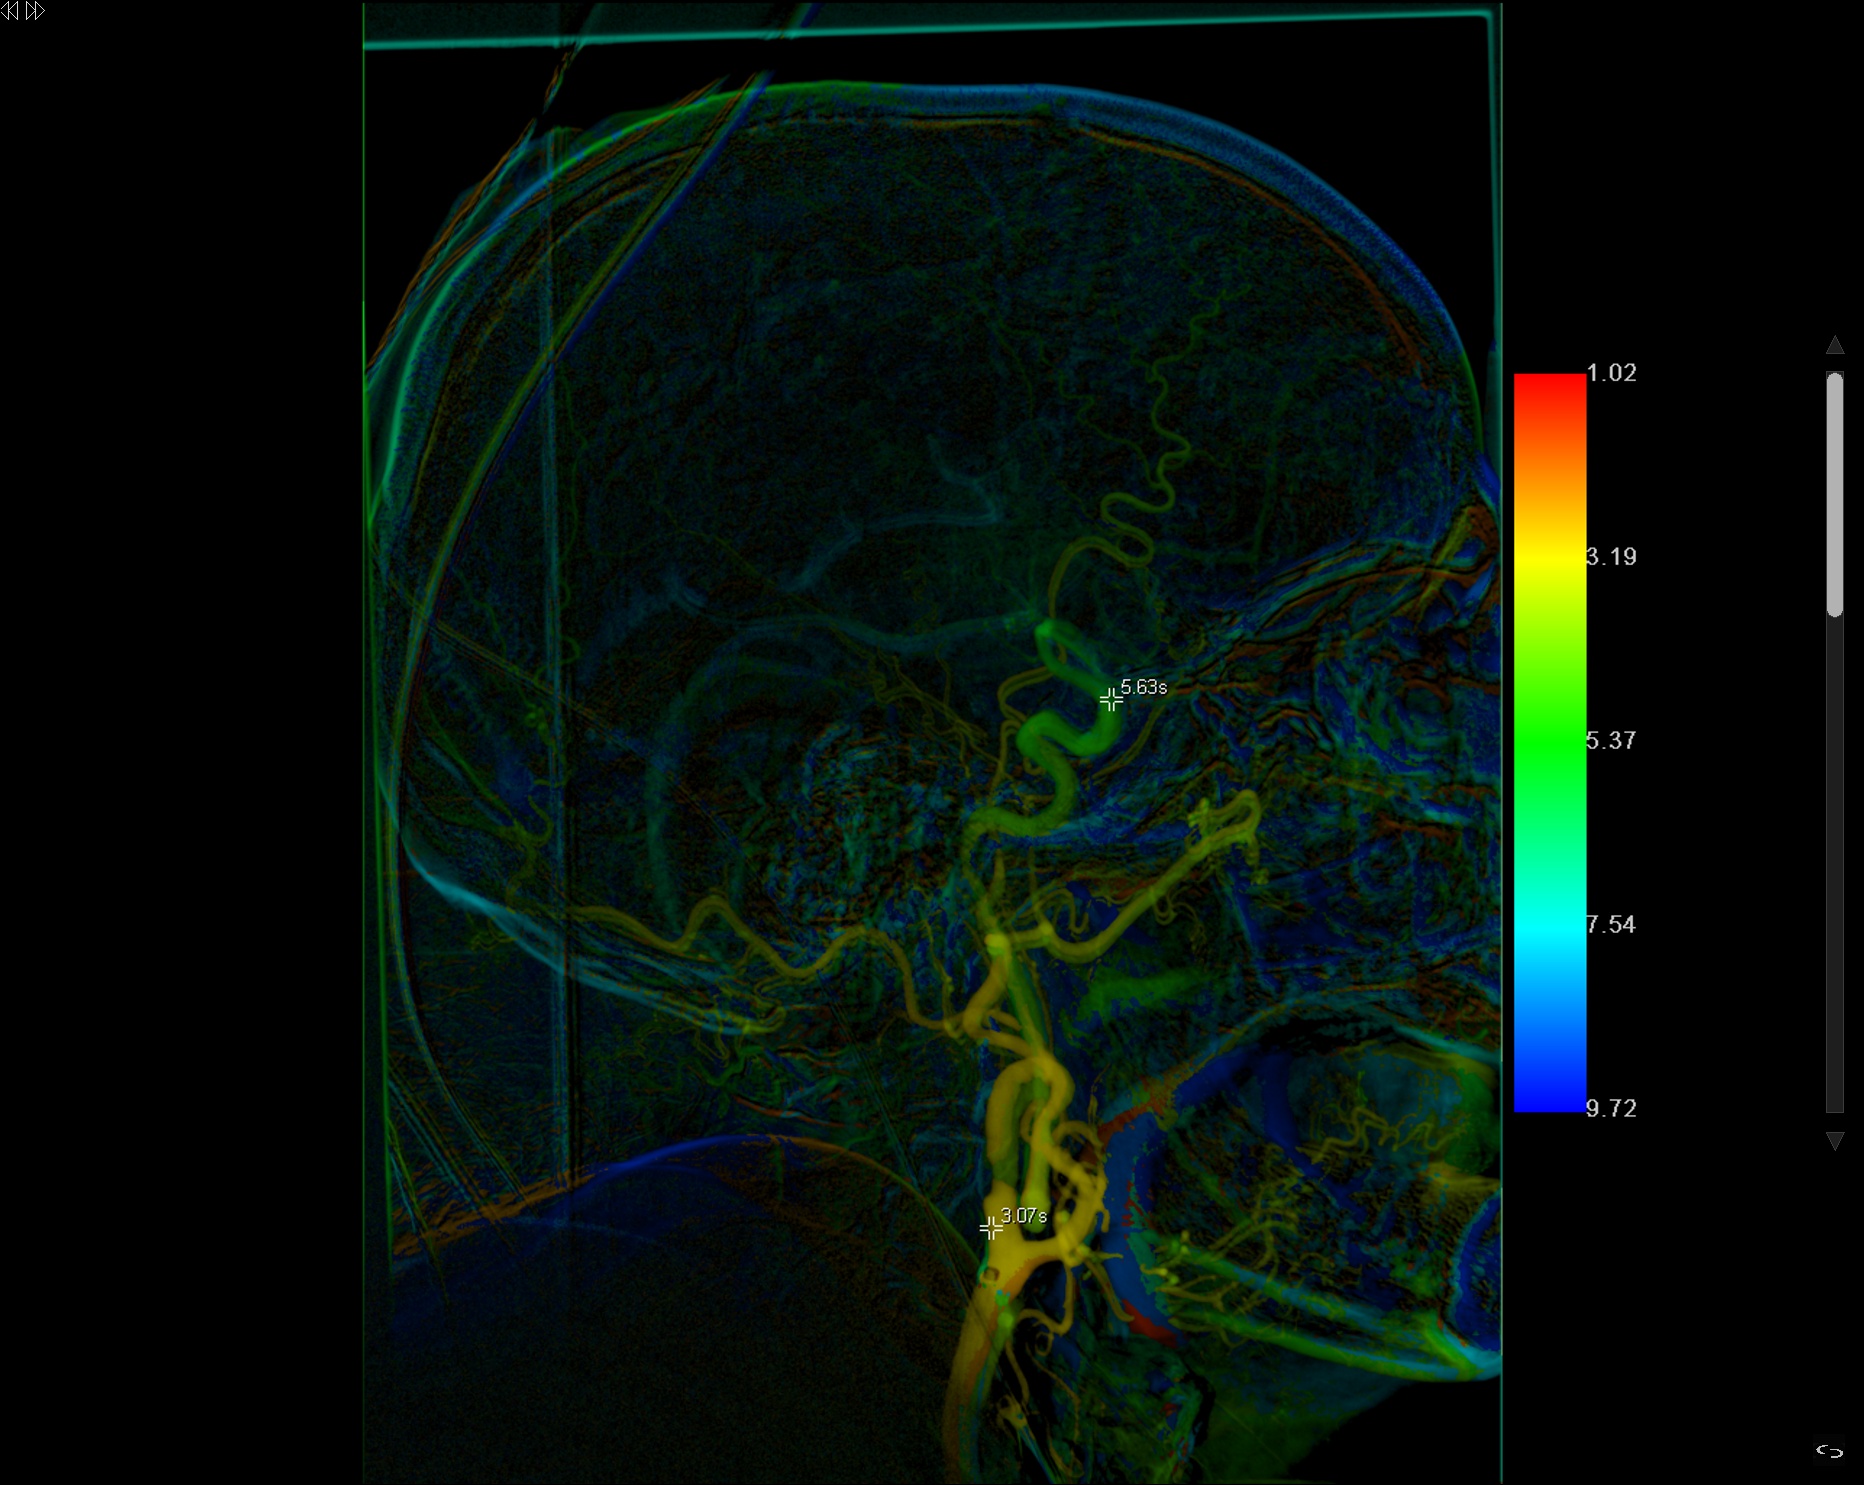

Se decide colocación de STENT en carotida interna

Comparativa pre y postratamiento utilizando la herramienta IFLOW